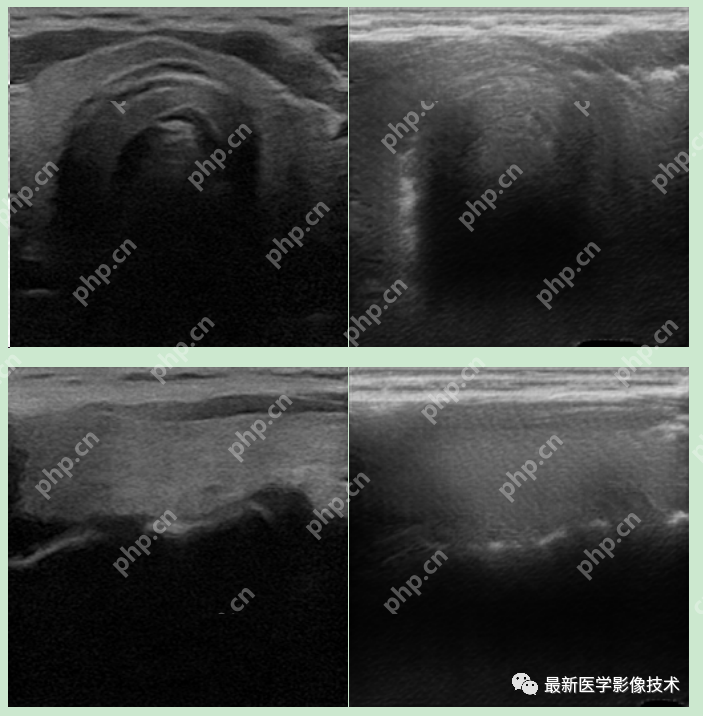

5、验证集部分生成结果

左图为低质量图像,中间为生成的高质量图像,右图为真实的高质量图像。